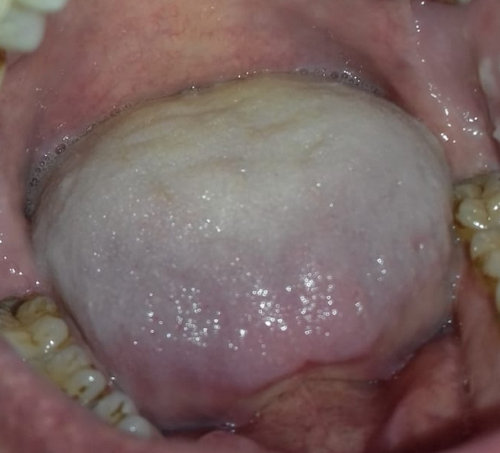

Недавно пришла цитология, где подтвердилась лейкоплакия твердого неба, вдобавок кандидоз полости рта. Пародонтолог прописал "Флуконазол" 5 дней по 50 мг, а пятно с лейкоплакией обрабатывать масляным раствором "витамина А" и "витамина Е" один раз в день на ночь, ротовые ванночки "Септомирин" в течение месяца.